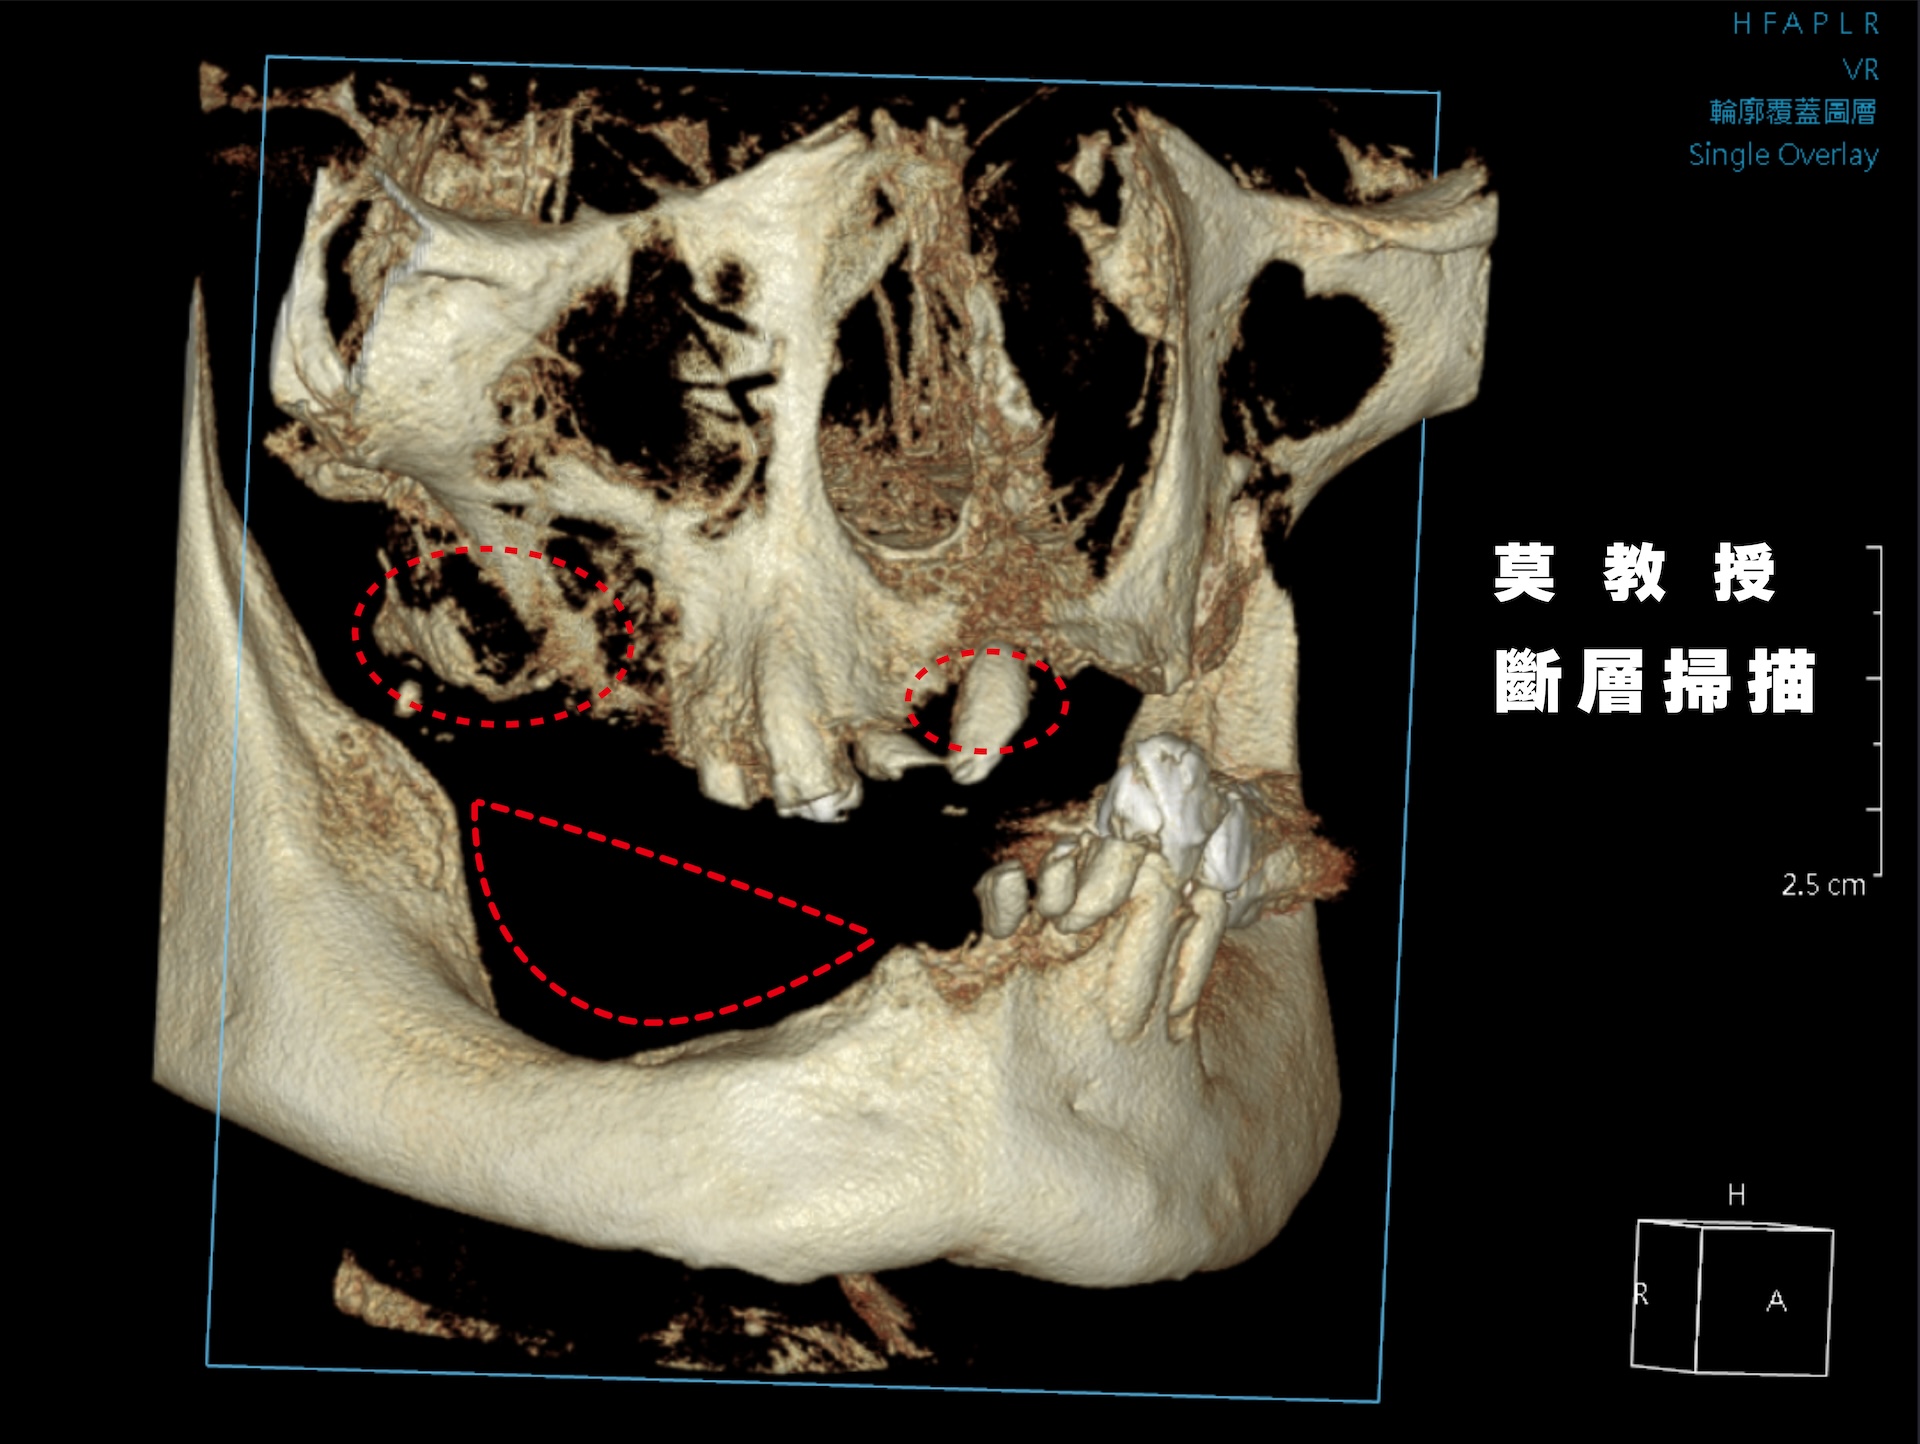

蒔美全口重建中心主任、口腔顎面外科專科賴泓璋醫師透過全頭顱電腦斷層與數位口掃精準評估齒槽骨與牙齦狀態,再深入了解他對咬合、外觀與生活品質的需求。

Dr. Hung-Chang Lai, head of the Full-Mouth Reconstruction Center, used craniofacial CBCT scan and a 3Shape intraoral scanner to assess his condition, then listened closely to his concerns.

賴醫師回憶:「第一次檢查時,莫教授就說想立刻裝上固定假牙。但我坦白告訴他:你的骨頭條件有限,尤其是上顎,骨質薄弱,甚至距離鼻竇不到 3 公釐,因此當天無法立即裝上固定假牙。不過,我們會先為你製作臨時活動假牙,既能維持自然外觀,也提供基本咀嚼功能。」

Dr. Lai recalled, “During our first consultation, Professor Mo told me he wanted to have permanent teeth fitted right away. I had to be honest with him: his bone structure, especially in the upper jaw, was too weak, and the distance to the sinus was less than three millimeters. That made it impossible to place permanent teeth on the day of surgery. Instead, we prepared a temporary set of removable teeth, which would preserve a natural appearance and allow basic chewing function.”